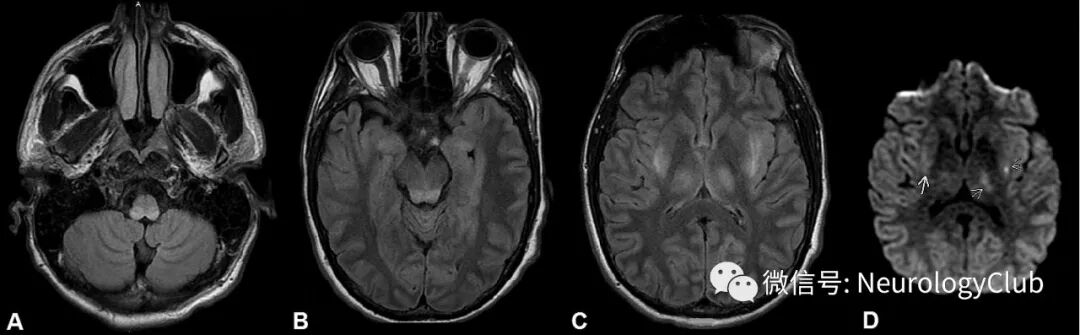

38岁男性,既往体健,无药物滥用史,在进食未煮熟的牛肉后出现呕吐和血便5天。其被诊断为溶血性尿毒综合征,送入重症监护病房。尽管采取了积极的抗生素和透析治疗,但患者意识状态仍在恶化,出现3次全面性强直阵挛发作,入院第7天予气管插管。脑电图(EEG)提示起源于后头部的局灶性癫痫发作。头颅MRI可见对称性后部菱脑炎伴双侧丘脑受累(图1)。脑脊液检查提示轻度细胞数增多(白细胞:31,中性粒细胞:98%),蛋白(133mg/dL)和葡萄糖(92mg/dL)升高。入院第7天时血清白蛋白从刚来时的4.7g/dL降至2.3g/dL。请神经科会诊。初次检查时,患者意识不清,没有发现明显的颅神经或局灶性神经功能缺损。

(图1:可见累及双侧丘脑和背侧脑干[中脑、脑桥和延髓]的FLAIR高信号病灶[A-C]和散在局灶性轻度弥散受限[D])

典型的MRI表现包括导水管和第三脑室周围区域以及丘脑,中脑和乳头体的T2-FLAIR高信号病灶,但非典型表现可为DWI上的可逆性弥散受限,而乳头体不受累,正如本例患者。